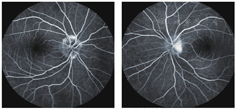

患者女,43岁。头痛3个月加重伴双眼胀痛、视力下降4天于2014年2月24日来我院眼科就诊。患者自述3个月前无明显诱因出现头颈部疼痛,呈跳痛,有时伴恶心,无呕吐,头痛发作前眼前无闪光、暗点等,亦无肢体麻木乏力感,无耳鸣、听力下降。于当地医院给予甘露醇治疗有效,但反复发作。入院眼部检查:双眼视力:0.8,双眼结膜无充血,角膜清亮,瞳孔直径约3 mm。对光反应稍迟钝,RAPD(+)晶状体透明,玻璃体清。双眼底:视乳头色淡红,边界不清,水肿隆起约2~3 D,视网膜静脉迂曲扩张,黄斑中心反光弥散,视网膜平伏(图1)。右眼压:12.5 mmHg,左眼压:11.0 mmHg。患者既往有冠心病史,于2010年在江西省人民医院行冠脉支架术。无糖尿病、高血压,无外伤等病史。血常规检查:血小板计数:580×109。脑脊液压力:250 mm H2O(正常120~180),显微镜及生化检查未见异常。眼底荧光素钠血管造影示:双眼视盘水肿(图2)。颅脑MRI、MRV、CT、眼眶CT均未见明显异常(图3)。全脑血管造影(CTA)示:考虑右侧横窦、乙状窦静脉血栓形成可能性大(图4)。明确诊断为:颅内静脉窦血栓形成,特发性血小板增多症,冠心病。